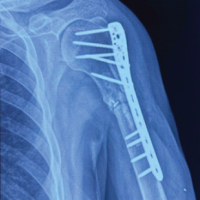

After thorough clinic-radiological and histological evaluation, she was planned for en bloc resection of the first metatarsal, reconstruction with vascular transfer of the second metatarsal to the first metatarsal, and amputation of the second toe. Magnetic resonance angiography was done to assess the vascular status of the first and second metatarsals.

An elliptical incision was taken around the previous scar, extended proximally and distally. The previous scar was excised along with the underlying subcutaneous tissues. The extensor hallucis longus tendon was retracted laterally, and en bloc resection of the first metatarsal was done. Wedge was made in medial cuneiform articular surface, vascular transfer of the second metatarsal was done to the first ray (Fig. 4).

A five holed 2.7 mm semitubular plate was used to stabilize the metatarso-cuneiform joint and a K-wire for metatarso-phalangeal joint, the base of second metatarsal was fused with intermediate cuneiform to maintain the arch support (Fig. 5).